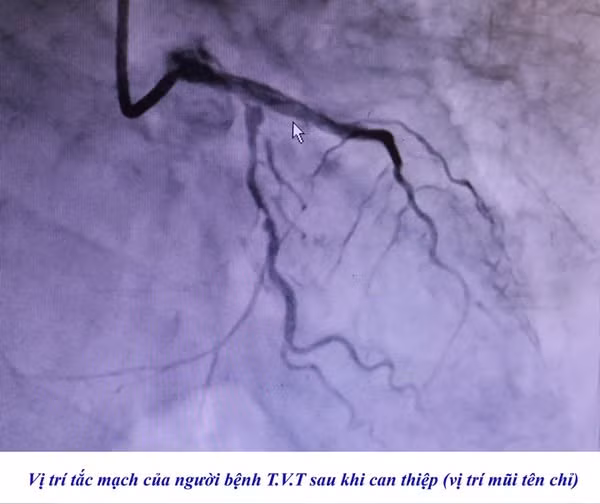

Nhập viện với triệu chứng đau tức ngực trái, đau dữ dội theo cơn, khó thở, 2 người bệnh được gia đình đưa đến cấp cứu tại Bệnh viện. Các bác sĩ nhận định cả 2 trường hợp đều có biểu hiện của nhồi máu cơ tim cấp nghi do hẹp tắc mạch vành cấp, ngay trong đêm các bác sĩ đã chỉ định chụp và can thiệp động mạch vành cấp cứu cho người bệnh....

| Hình ảnh tắc mạch vành trên phim chụp - Ảnh BVCC |

Các bác sĩ Bệnh viện Việt Nam – Thụy Điển Uông Bí cho biết, phương pháp can thiệp nội mạch, đặt stent là phương pháp can thiệp tối ưu cho người bệnh nhồi máu cơ tim. Sau can thiệp tỷ lệ thành công cao, người bệnh hồi phục nhanh chóng.